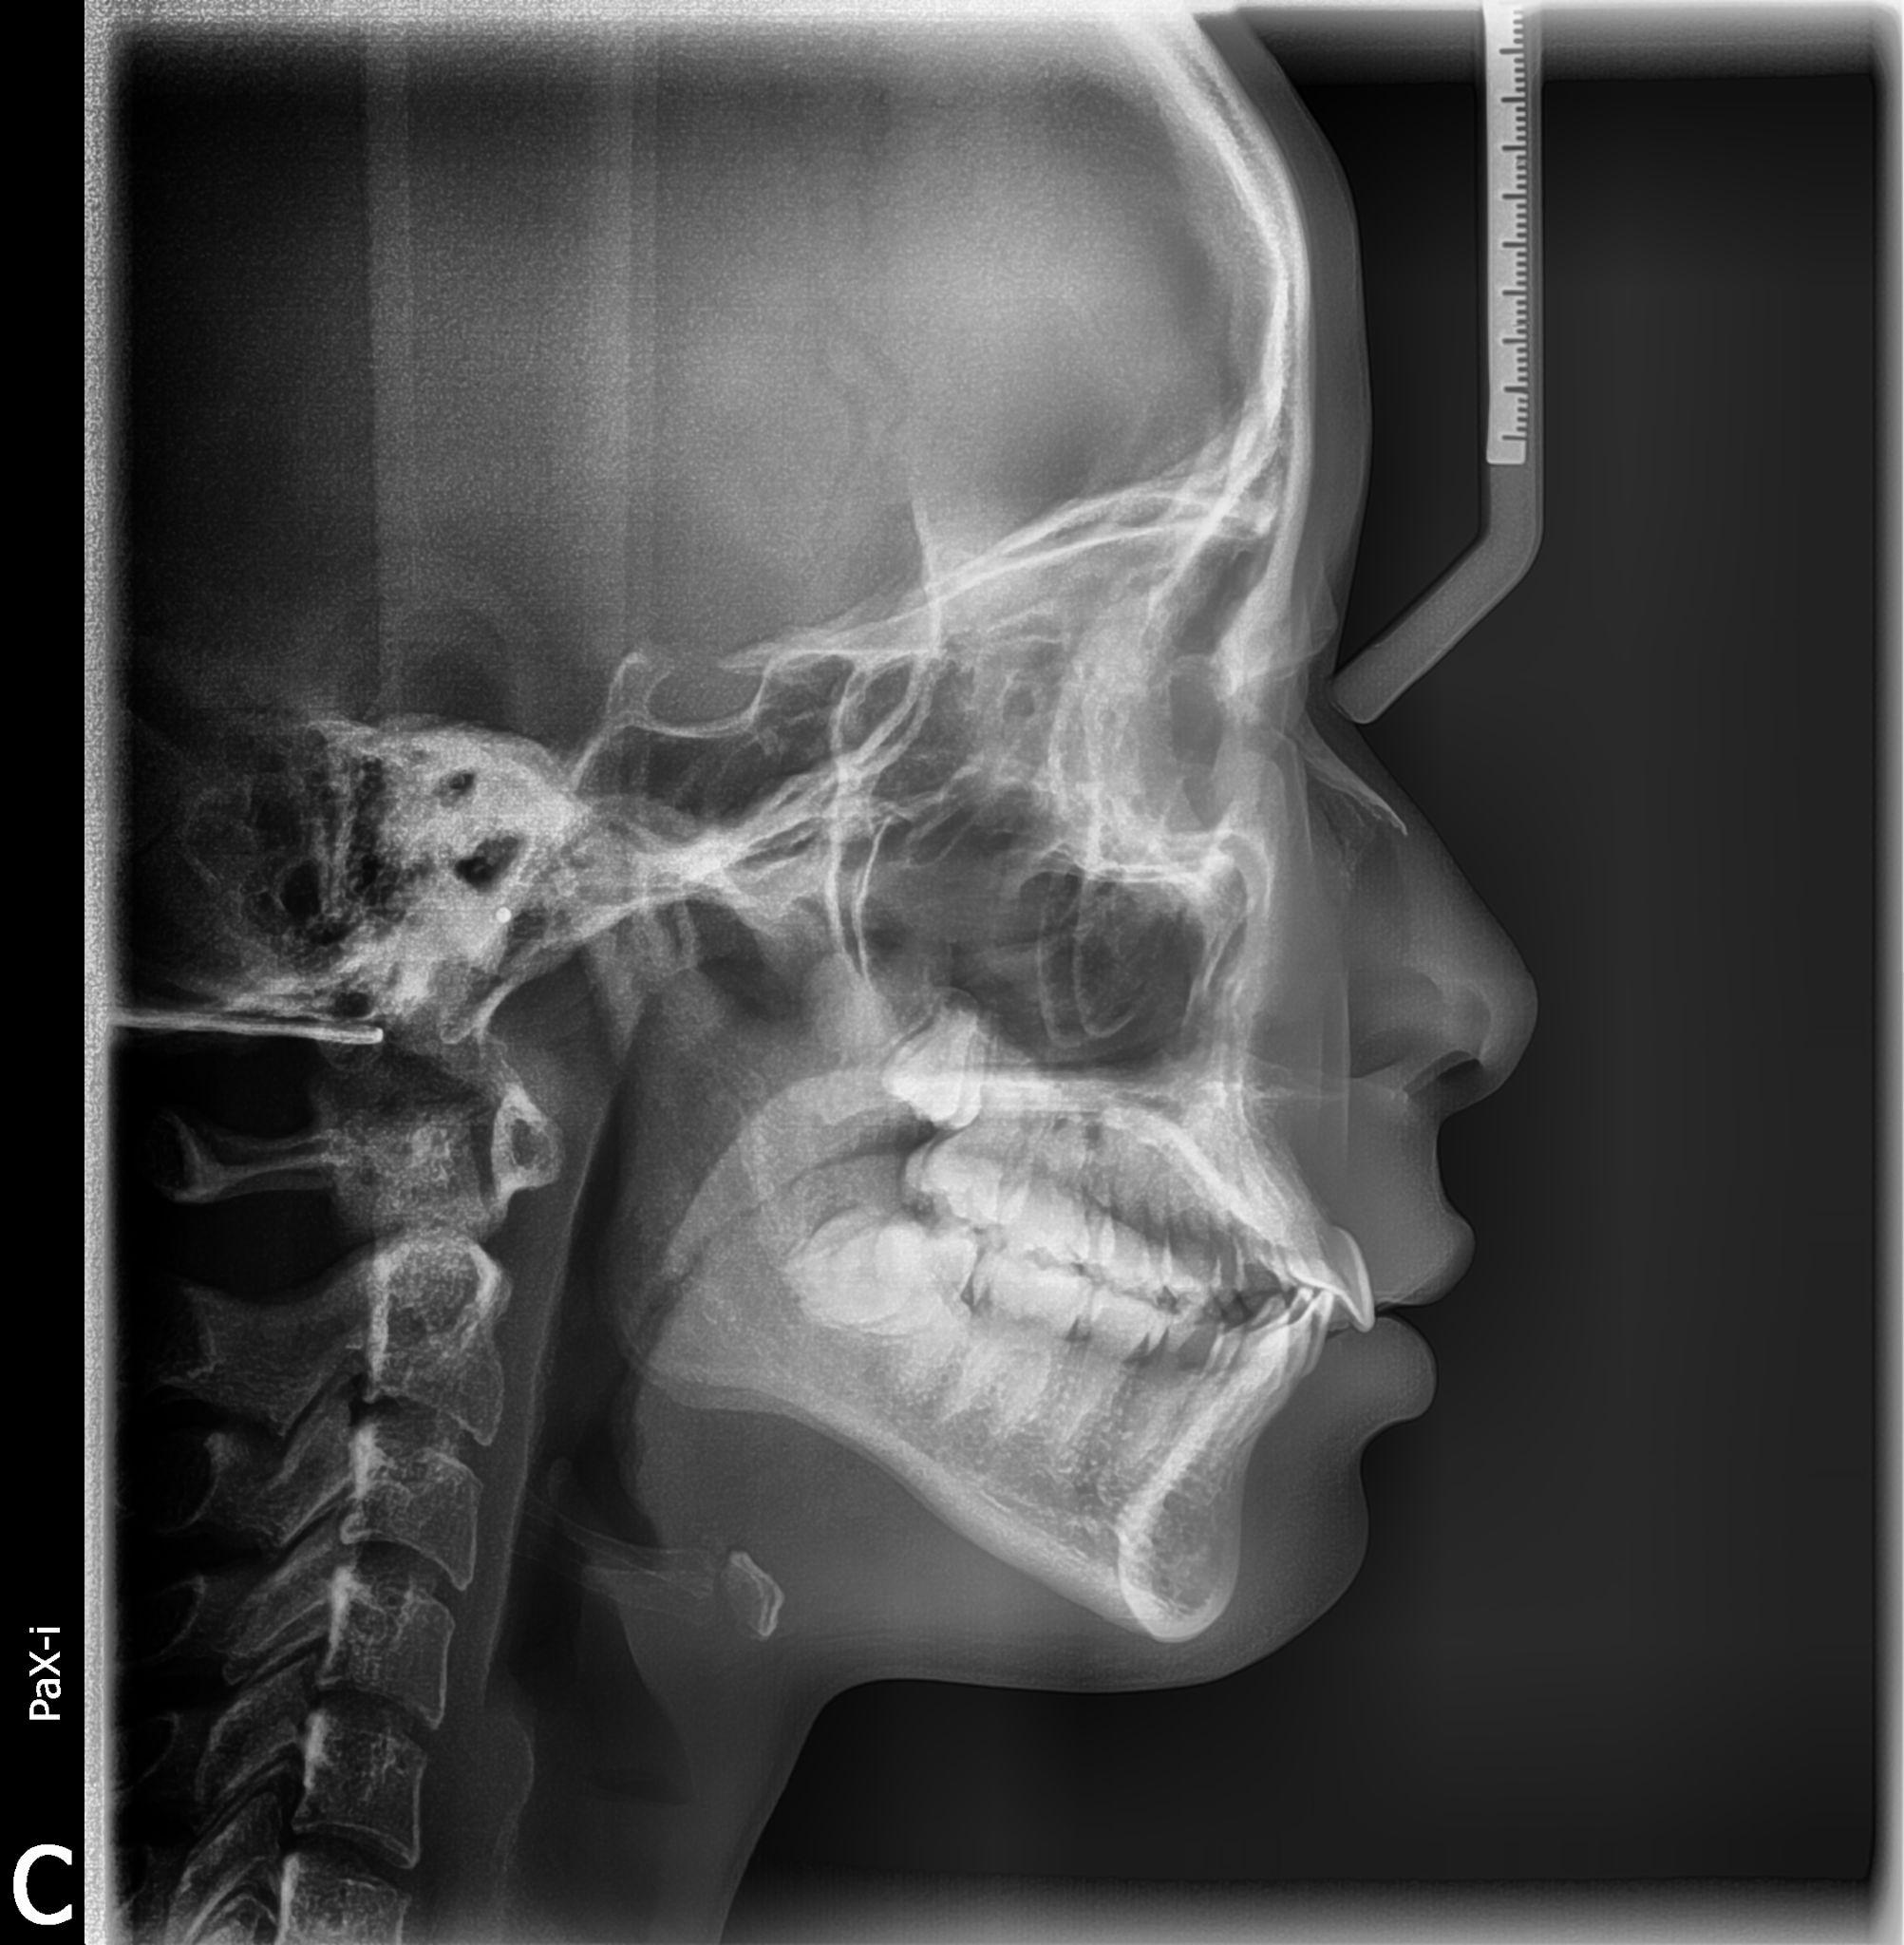

在正规的三甲医院口腔科进行口腔CT的拍摄,费用大概在450元左右CT可以直观的,看出炎症的位置,以及炎症的扩散面积和牙齿的立体结构,能够彻底的看清楚炎症的位置,是理想治疗牙齿的拍摄方式,也是大多数正规医院的口腔科,所采取的术前片术中片和术后片的方式,口腔CT对而患者的牙齿显示度较好,通常。

选择医院北大口腔作为专科医院,设备先进如CT医生经验丰富,尤其适合复杂阻生齿病例专家号优先复杂阻生齿拔除难度高,专家操作可降低神经损伤术后感染等风险,尽管挂号难,但长期看更安全高效术后护理遵循医嘱如24小时内冰敷避免剧烈运动饮食清淡可减轻肿胀和疼痛,促进愈合个体。